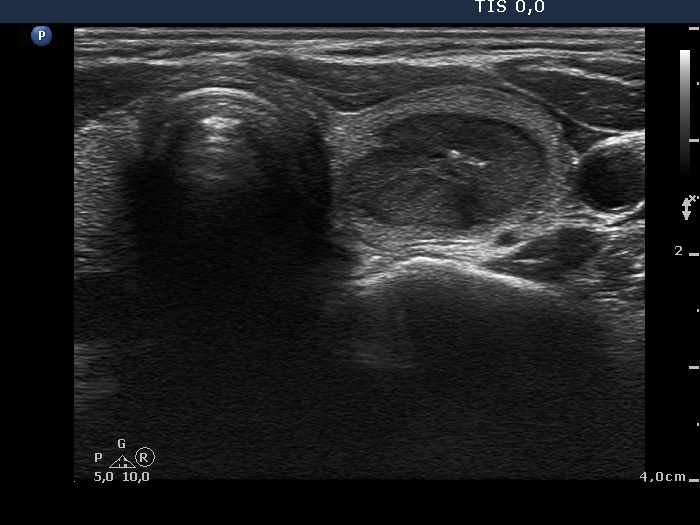

Ethanol sclerotherapy: thyroid cysts - Case 11

Three years after the sclerotherapy (ultrasonographic picture 1)

Left lobe, horizontal scan. The lesion is a bit larger compared with the previous size. Note the presence of intranodular hyperechogenic granules.